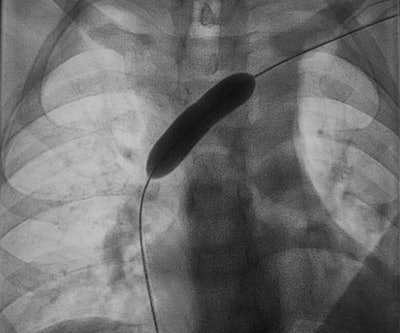

A: In the case of thromboses, we offer the option of removing thrombi in interventional radiology. We reopen vessels that have become diseased due to chronic occlusion caused by thrombosis, and we can insert stents there to achieve outflow, for instance. We access mainly via the blood vessels -- i.e., arteries or veins -- with the help of catheter technology.